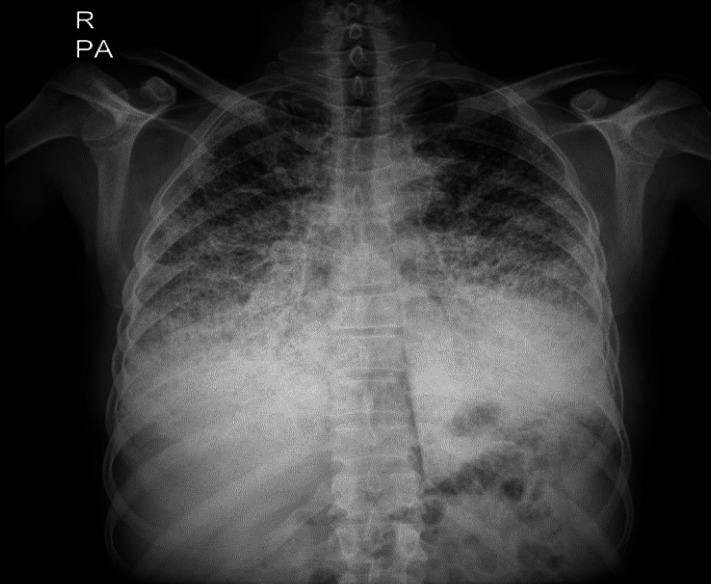

Case presentation: Herein, we have reported a 50-year-old male presented with recent sore throat, fever, and sweating. Radiological findings revealed bilateral micronodular pattern with diffuse ground glass attenuation in lower regions. Subsequent histologic examination of lung biopsy confirmed intra-alveolar accumulation of calculi and the diagnosis of PAM. In addition, we reviewed the literature narratively to clarify different aspects of PAM.

Conclusion: In this paper, we presented a sporadic case of PAM which was suspected with chest x-ray and confirmed by HRCT and trans-bronchial lung biopsy. We hope that it can help clinicians to be more aware of this condition and make proper diagnosis.